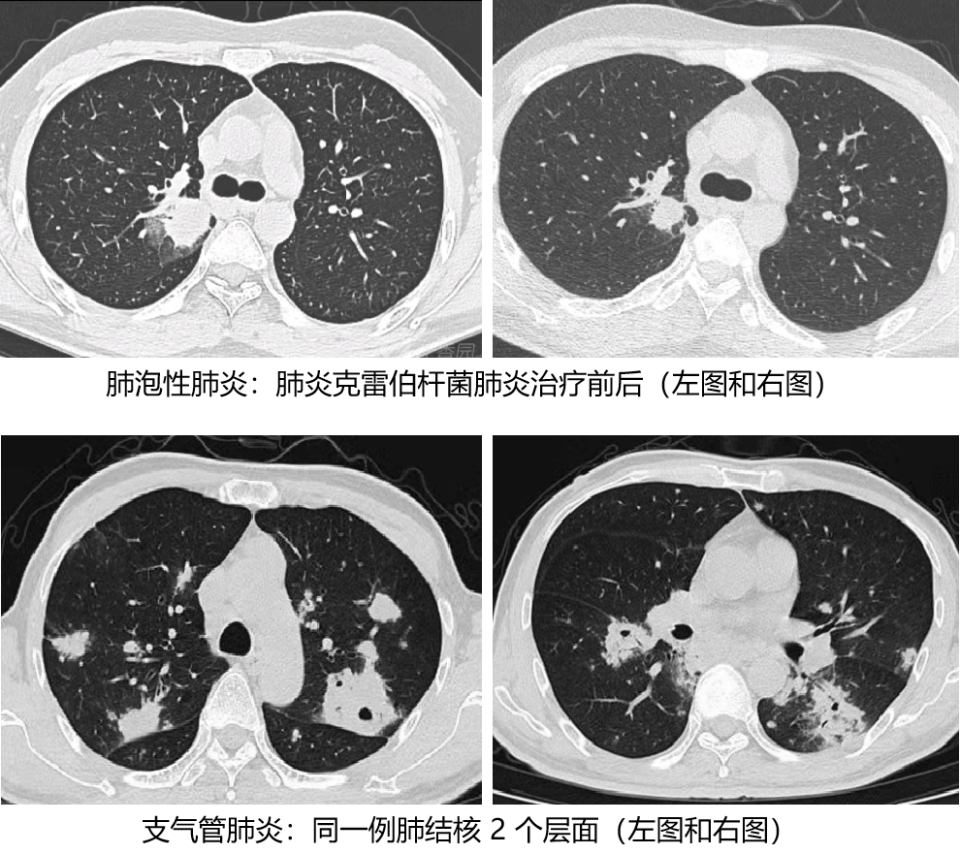

肺炎是指终末气道肺泡和肺间质的炎症, 可由病原微生物、理化原因、免疫损伤、过敏及药物所致,以细菌性肺炎最常见。根据生理解剖位置分为:(1) 肺泡性肺炎;(2) 支气管肺炎;(3) 间质性肺炎。分清这三种解剖分类的肺炎,对通过影像判断微生物,经验性抗生素治疗有指导作用,下面我们一起来学习。

1. 肺泡性肺炎:细支气管没有炎症,肺泡内有炎性渗出,连成大片,肺泡间隔不增厚/或增厚。

2. 支气管肺炎:细支气管壁增厚,炎症细胞浸润,围绕细支气管周围肺泡有渗出,呈岛状,附近有少量的肺泡正常,远处有大量的肺泡正常。

1. 肺泡性肺炎:由多个肺小叶组成亚段或段的片状影,严格按解剖区域出现(肺链最典型,军团、肺克稍差)。

2. 小叶性肺炎(支气管肺炎):以支气管为中心的小片状影。

1. 大叶性肺炎(肺泡性肺炎):渗出性病变占满一个或几个肺叶,这时称大叶性肺炎。

2. 支气管肺炎:渗出性病变也可以融合后占据一个肺叶,注意这种情况仍不能称其为大叶性肺炎,本质上支气管有炎症,灵魂是始终有支气管炎。

五. 3 种肺炎常见的致病菌

1. 肺泡性肺炎(大叶性肺炎):肺炎链球菌肺炎、肺炎克雷伯杆菌肺炎、军团菌肺炎及肺隐球菌病。

2. 支气管肺炎(小叶性肺炎):金黄色葡萄球菌肺炎、铜绿假单胞菌肺炎、流感嗜血杆菌肺炎、大肠埃希菌肺炎、阴沟杆菌肺炎、肺结核及非结核分枝杆菌肺炎、支原体肺炎、肺念珠菌病、丝状真菌肺病等。